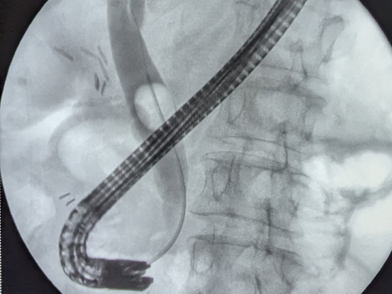

Основной особенностью, внедрённой в широкую клиническую практику методики, является одномоментное сочетанное использованием двух миниинвазивных технологий. Операции выполняются при помощи специального оборудования через небольшие проколы передней брюшной стенки и через ротовую полость пациентов.

Хирурги Клиники №1 ВолгГМУ Минздрава России внедрили в клиническую практику и с начала года выполнили 30 одномоментных операций пациентам с осложненным течением желчнокаменной болезни.